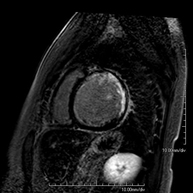

- Shoulder MRI

Examination to study injuries to tendons, muscles and joints. Its main use is to diagnose injuries to the rotator cuff tendons. It lasts approximately 20 minutes. It is a radiation-free procedure.